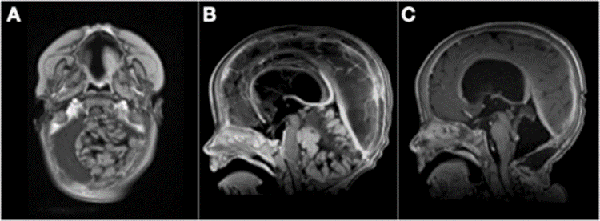

Analizando por separado los resultados de anatomías patológicas vemos que los ATRT, meduloblastomas y ependimomas tuvieron una supervivencia del 32% a los 5 años (Figuras 3 y 4) y los pacientes con tumores embrionarios, PNET, carcinomas y papilomas atípicos de plexos coroideos y pineoblastomas presentaron una mortalidad del 100% a los 5 años (Figuras 5 y 6). Por otro lado, los papilomas de plexos coroideos, lesiones más frecuentes en el grupo 1, tuvieron un 100% de supervivencia a los 10 años, al igual que los astrocitomas y gliomas de bajo grado (Figuras 7 y 8).

Figura 7: A) Paciente de 13 meses, sexo masculino, consultó por alteraciones en la motricidad. TC de cerebro con contraste EV que evidenció lesión intraventricular que realza homogéneamente e hidrocefalia, se colocó DVE previo a cirugía de exéresis tumoral. B) TC de cerebro luego de cirugía, diagnóstico de papiloma de plexos coroideos, se retiró el DVE a las 48 hs. TC de cerebro de control al año con colecciones subdurales crónicas. Se decidió conducta expectante de las mismas. C) IRM de cerebro control a los 3 años, sistema ventricular de tamaño normal, corticotomía cerrada. Paciente sin secuelas neurológicas.

Figura 8: A y B) Paciente de 21 meses de vida, sexo femenino, que presentó hemiparesia faciobraquiocrural derecha, vómitos y deterioro del sensorio, TC de cerebro con contraste EV, lesión supra e infratentorial, con gran efecto de masa con compresión del tronco del encéfalo. Se realizó cirugía de exploración y exéresis parcial. Anatomía patológica informó papiloma de plexos coroideos. C y D) IRM de cerebro con contraste EV que evidenció resto tumoral intraventricular y en relación a cisternas peri mesencefálicas. Se realizó re exploración del tumor. E y F) Imagen por TC de cerebro con contraste EV postquirúrgica inmediata que evidenció exéresis total.